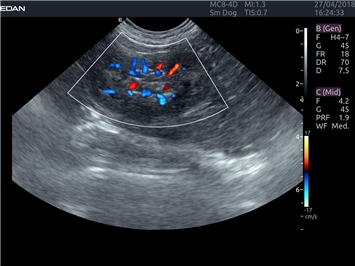

EDAN Acclarix LX4 VET представляет собой профессиональную ультразвуковую систему, специально разработанную для ветеринарных исследований. Сочетание стабильности, высокой производительности и эффективности делает эту систему идеальным выбором для современной ветеринарной практики.

Режимы акустической прозрачности 3D:

Да

Трехмерная реконструкция ЦДК:

Энергетический допплер:

Цветовой допплер: